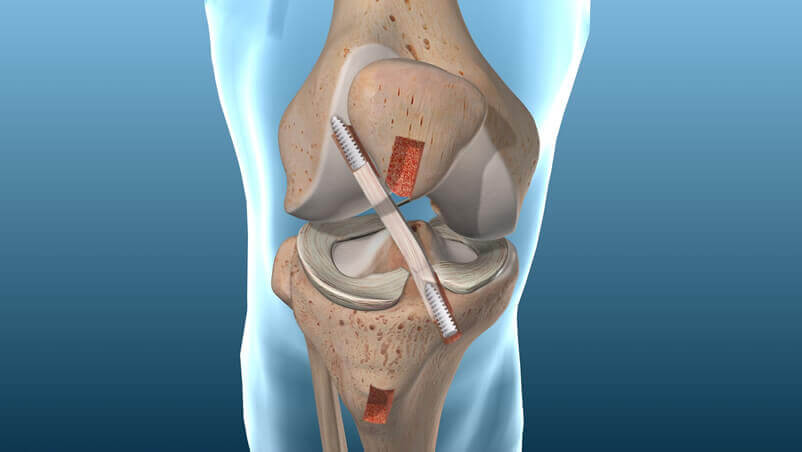

Biaya operasi ACL di Indonesia sangatlah beragam. Hal tersebut tergantung dari jenis pelayanan medis yang dipilih. Jika Anda menggunakan BPJS…